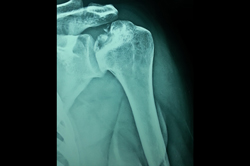

Shoulder Replacement